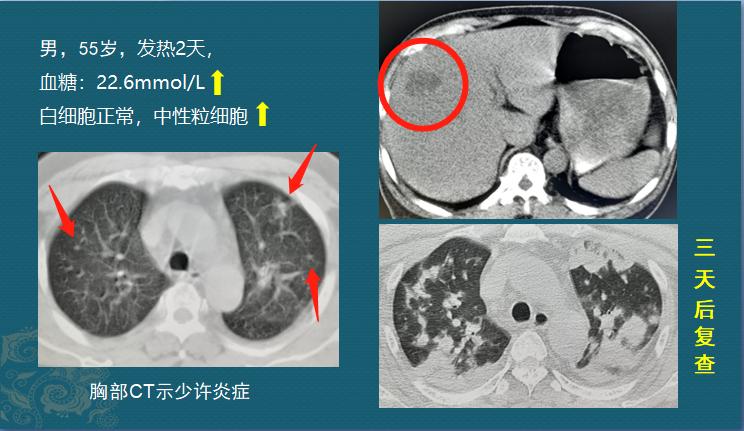

我们看个病例了解一些这种肺炎克雷伯肺炎的凶猛进展:

55岁男子,发热2天,最高体温38.2℃,伴有呼吸急促,化验白细胞计数不高,中性粒细胞略升高,胸部CT发现双肺少量炎症(左图红色箭头),肝脏低密度影提示肝脓肿。

判读这些检查结果,有些人可能会觉得病情不怎么严重,口服点消炎药就能好,没必要大惊小怪地住院吧。

其实病情已经很重了!医生注意到他的血糖升高到22.6mmol/L,比正常人高了接近4倍,而且已经出现了糖尿病酮症、氧分压减低,口唇轻度紫绀,过度通气等表现,病情很危重!

3天后复查CT,果然双肺表现出了大量细菌繁殖感染的表现,重症肺炎了(右图)。

由于长期高血糖状态,肠道内的肺炎克雷伯菌利用糖分大量繁殖,顺着血管和胆管进入他的肝脏和肺脏,这种现象称作肠道定植菌异位,细菌失去管制四处流窜,跑到肝脏和肺部引起肝脓肿、重症肺炎,属于肺炎克雷伯菌肝脓肿侵袭性综合征了。这位病人后来在重症监护病房住了20多天才痊愈,花费不少。